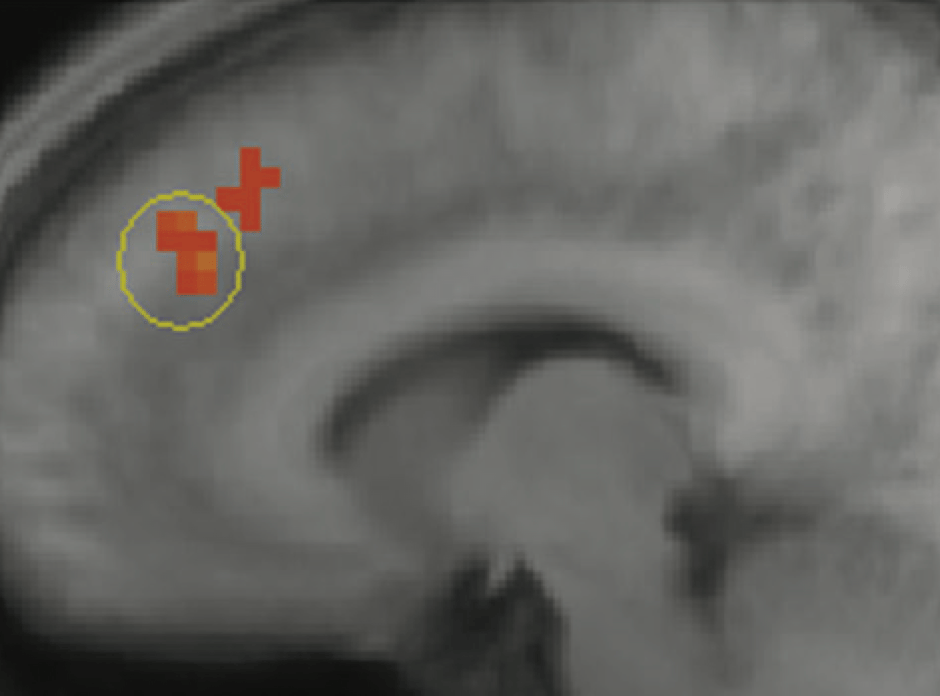

This gets surprisingly scientific. Researchers in the field of “neuroeconomics” have identified an area of the brain — the paracingulate cortex — that activates in top traders when insider trading is present in a market.

The area of the brain that lights up when something feels off — the odd behavior of someone hiding a secret, say — also lights up when market behavior suggests someone’s hiding insider information.

A scan pinpoints the part of the brain that’s triggered when a skilled trader gets the sense that someone knows something: